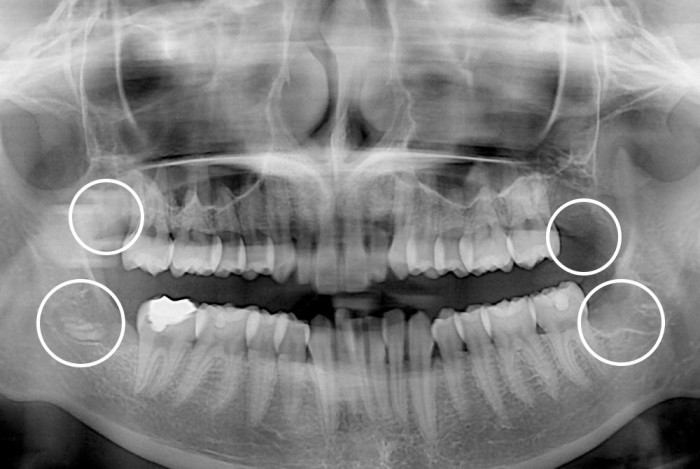

치료후 : 2019-03-13

세종치과는 구강악안면외과학 박사이신 원장님이 발치하는 치과입니다.